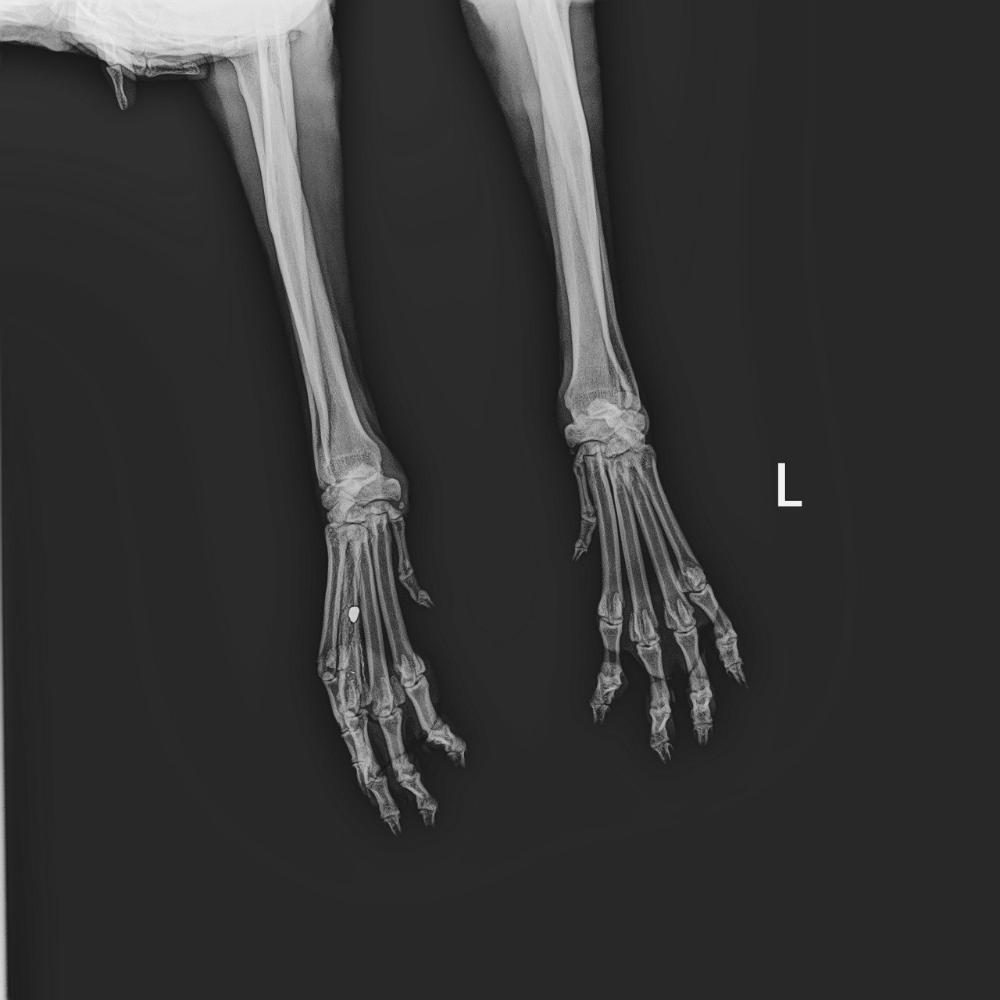

Нечаева и Ко Опубликовано 16 декабря, 2025 Опубликовано 16 декабря, 2025 (изменено) Наши новости. Господи, что ни день, то сюрпризы😥 Изменено 16 декабря, 2025 пользователем Нечаева и Ко 1 4